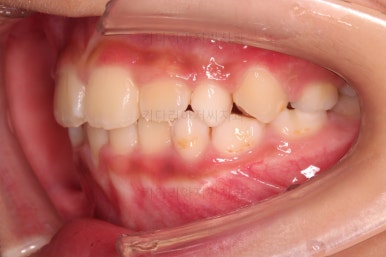

무려 4개월 만에 부산어린이교정 치료가 종료되었습니다.

앞니의 교합이 매우 안정적이여서 치료를 끝냈고요.

전후 비교해 보겠습니다.

반대교합이 완벽히 개선되면서 주걱턱으로 보였던 얼굴형태도 완벽히 개선되었고요.

한 쪽으로 치우치던 아래턱의 위치도 돌아오면서 비대칭이 개선되었습니다.

심지어는 위아래 앞니가 삐뚤었던 부분도 일정 부분 좋아졌습니다.

반대교합으로 인해 아래 앞니 잇몸 퇴축이 있었던 부분은 되돌아오지는 않는 점이 아쉽습니다.